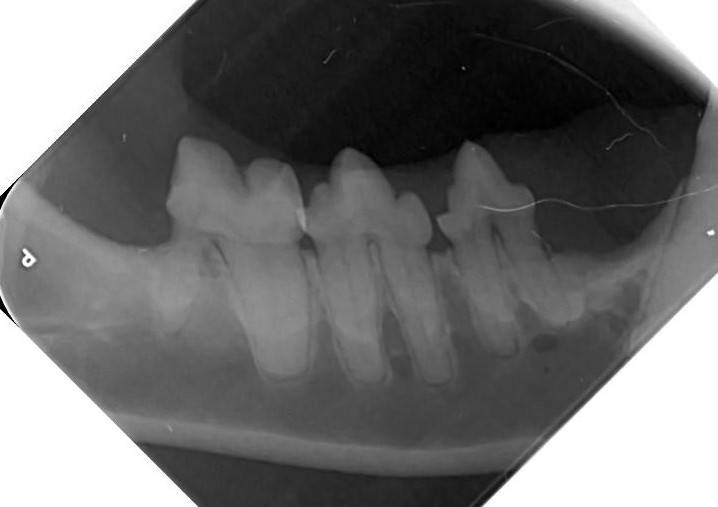

Nouveau : Radiologie dentaire chien ou chat

La clinique Vétérinaire est équipée d'un appareil de radiologie dentaire XMind accompagné d'un systême de développement numérique.

Cet équipement est indispensable à la réalisation d'un bilan dentaire complet sur un chien ou un chat. En effet, la majorité des lésions dentaires chez les carnivores se trouvent sous la gencive et ne se voient pas à l'oeil nu, en particulier les résorptions dentaires chez le chat C'est pourquoi nous conseillons un bilan dentaire lors d'une intervention buccale ou un détartrage de convenance.

toute radiologie dentaire ne peut être effectuée que sous sédation profonde afin que le cliché puisse être effectuée et afin d'obtenir une bonne qualité d'image.

Celà permet de dépister des dents fracturées, abîmées, infectées, les lyses osseuses de la mâchoire. Une infection dentaire latente peut être responsable de complications rénales cardiaques ou hépatiques